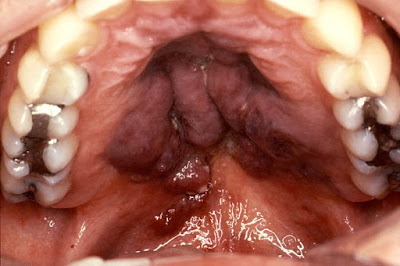

Καρκίνος στόματος: Ο καρκίνος που εμφανίζεται στην στοματική κοιλότητα έχει τριάντα μορφές. Όμως, η πιο συχνή περίπτωση έχει να κάνει με το ακανθοκυτταρικό καρκίνωμα. Ο στοματικός καρκίνος εντοπίζεται συχνότερα σαν ανώδυνο έλκος. Η συγκεκριμένη πληγή δεν κλείνει. Αντίθετα, μεγαλώνει. Έτσι, δημιουργεί προβλήματα, μάσησης, ομιλίας και κατάπωσης. Επίσης, μπορεί να εμφανιστεί και σαν λευκή πλάκα ή κόκκινη περιοχή. Μάλιστα, πολλές φορές η ανάπτυξή του ακολουθεί προκαρκινικές βλάβες. Αναλυτικότερα, όλα όσα οφείλετε να γνωρίζετε για τον καρκίνο του στόματος:

Ο στοματικός καρκίνος εμφανίζεται συνήθως σαν ένα ανώδυνο έλκος (πληγή) στην αρχή, που δεν κλείνει με την πάροδο του χρόνου, αντίθετα μεγαλώνει δημιουργώντας προβλήματα στη μάσηση, την ομιλία ή την κατάποση. Μπορεί να εμφανιστεί και σαν μια λευκή πλάκα ή μια κόκκινη περιοχή.